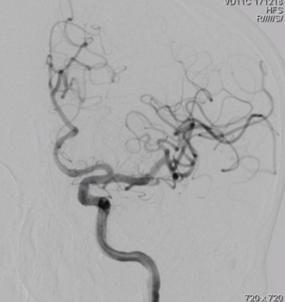

术前造影:

左侧颈内动脉C3段大动脉瘤,大小约23*11mm,瘤颈长度7.4mm,载瘤动脉远端直径约3.8mm,近端直径约4.2mm。

再行造影见动脉瘤不显影,无造影剂渗漏,血管重建满意。

3D重建图示支架贴壁良好。